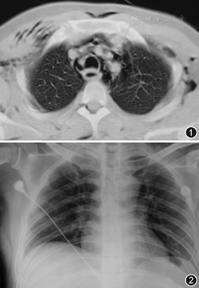

患者男,25岁,因"口干、多饮1个月余,食欲不振、乏力3 d,呼吸困难1 d"于2009年3月5日入院。患者1个月前出现口干、多饮症状,近3 d出现食欲不振、乏力、恶心、呕吐咖啡渣样物。患者近1个月来体重下降约10 kg。既往无高血压、糖尿病、慢性肺部疾病等病史。入院体检:体温36.4 ℃,脉搏120次/min,呼吸频率40次/min,血压115/72 mm Hg(1 mm Hg=0.133 kPa),呼吸深大急促,颈部、前胸壁及腹壁皮肤可触及握雪感,双肺呼吸音低,未闻及干湿性啰音,心率120次/min,律齐,无病理性杂音。血常规示:白细胞30.0×109/L,中性粒细胞0.89,红细胞为7.04×1012/L,血红蛋白196 g/L,血小板270×109/L。尿常规示pH值5.00,尿糖55 mmol/L,酮体14.4 mmol/L。随机血糖26.3 mmol/L,肾功能检查示尿素氮21.1 mmol/L,肌酐217 μmol/L,血电解质钠112 mmol/L,钾3.8 mmol/L,氯84 mmol/L。动脉血气(吸氧5 L/min)示pH值7.10,PaCO2为10 mm Hg,PaO2为139 mm Hg,HCO3–为3.1 mmol/L,BE–为23.8 mmol/L,SaO2为98%。胸部CT示食管扩张明显,食管壁部分增厚,胃内积气明显,纵隔积气,双侧前胸壁、腹壁可见皮下积气,未见食管及气管撕裂(图1)。初步诊断为糖尿病酮症酸中毒(DKA)、纵隔气肿、皮下气肿。立即给予补液、纠正酸中毒、普通胰岛素静滴降糖等对症处理,并行胃肠减压,引流出气体约600 ml,咖啡色液体约370 ml,行颈部上纵隔切开放置引流管引流纵隔积气。行胃镜检查示:食管及胃底见咖啡渣样物,十二指肠球部充血水肿,未发现明显食管及胃壁穿孔。经血清C肽释放试验及糖尿病自身抗体印迹杂交检查最后诊断为2型糖尿病,DKA,自发性纵隔气肿,皮下气肿。给予精蛋白生物合成人胰岛素注射液、重组人胰岛素常规笔芯及二甲双胍肠溶片控制血糖,经上述处理后患者病情明显好转,呼吸困难症状消失,2009年3月11日胸部X线检查示皮下气肿、纵隔积气基本吸收(图2)。2009年3月17日复查血常规、尿常规、肾功能、动脉血气、血电解质均恢复正常,血糖控制良好,尿糖、酮体均转为阴性,2009年3月19日出院。随访2年患者病情无复发,血糖控制良好。